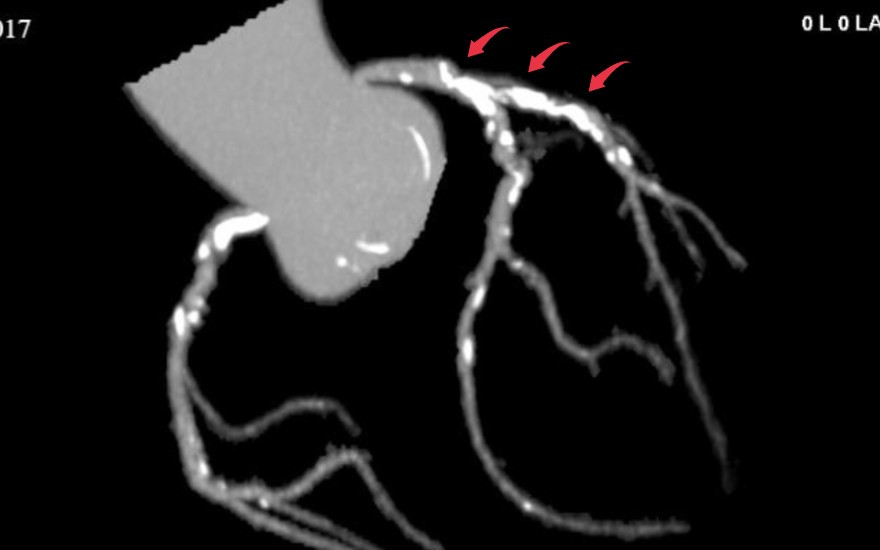

Kết quả chụp CT mạch vành 2560 lát cắt đã cho thấy hai nhánh mạch vành của ông N bị hẹp nặng. Trong đó, động mạch liên thất trước hẹp khít do mảng xơ vữa, vôi hóa kéo dài 30 - 35mm, còn động mạch vành mũ hẹp khoảng 80%.

Mảng vôi hóa lan tỏa trên hình ảnh chụp CT 2560 lát cắt - Ảnh BVCC